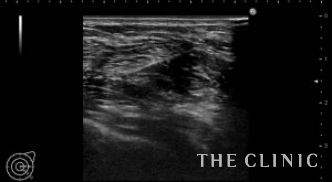

ベイザーで崩して吸引した脂肪と穿刺吸引したオイルです。